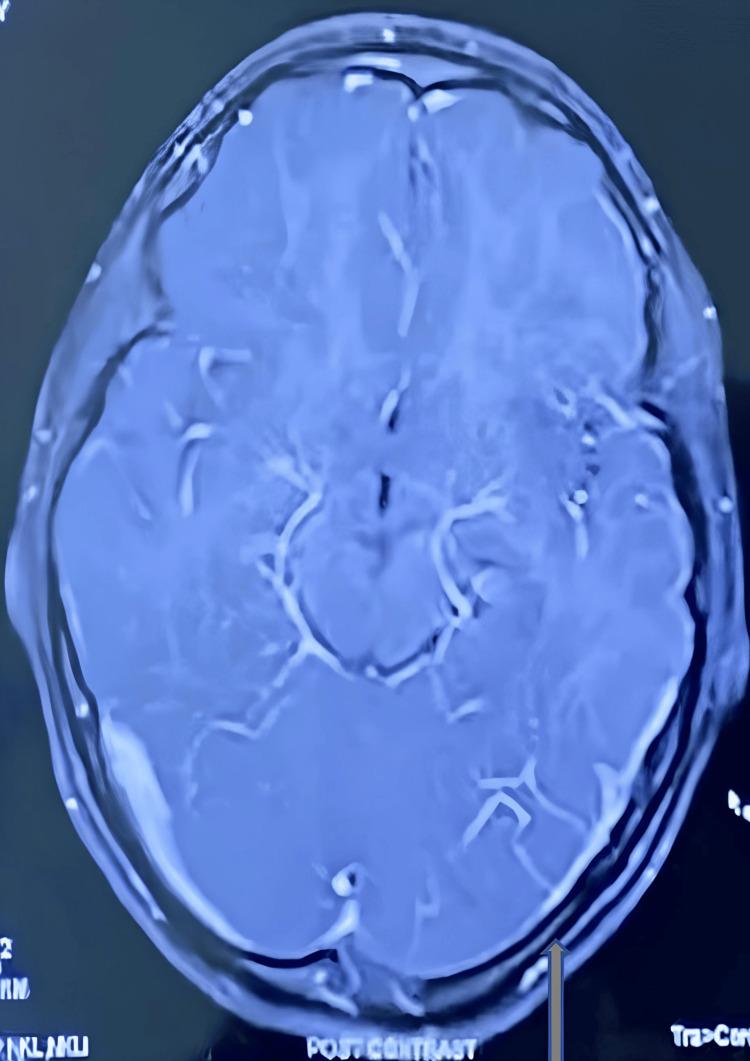

According to the literature, transverse sinus hypoplasia is not a normal variant and has a serious potential effect on cerebral blood flow. We are presenting a rare case of chronic headache due to severe hypoplasia of the left transverse and sigmoidal sinus. A 12-year-old female girl was admitted with a complaint of gradual progressive severe headache, throbbing in nature, confined to a bitemporal and frontal region in the last 4-5 months. Headache is not associated with fever, vomiting, photophobia, or vision problems. The child had no history of recurrent running nose, refractory vision, ear discharge, head trauma, exanthemata rash, or any drug history. On examination, the child was conscious and oriented. Vital signs are normal. The child was neurologically normal and had no focal signs. Other systemic examinations were normal. Based on History and examination, differential diagnosis was made, like Pseudo tumor cerebri, migraine, deep vein sinus thrombosis, and functional and Posterior fossa tumor. The child had normal routine investigations like complete blood count, electrolyte, and D-dimer. The fundoscopy was normal. In MRI, brain hypoplasia of the left transverse and sinusoidal sinus was suspected and confirmed by MRI venography. Thus, for any patient in an emergency with a chronic headache without focal signs and normal fundoscopy, one deferential should be considered for transverse and sigmoid sinus hypoplasia.

根据文献记载,横窦发育不全并非正常变异,对脑血流有严重的潜在影响。我们报告一例罕见的因左侧横窦和乙状窦严重发育不全导致慢性头痛的病例。一名12岁女童因逐渐加重的严重头痛入院,头痛呈搏动性,在过去4至5个月局限于双侧颞部和额部区域。头痛与发热、呕吐、畏光或视力问题无关。该患儿无反复流涕、难治性视力问题、耳漏、头部外伤、皮疹或任何用药史。体格检查时,患儿意识清醒、定向力正常。生命体征正常。神经系统检查正常,无局灶性体征。其他系统检查也正常。根据病史和检查结果,进行了鉴别诊断,如假性脑瘤、偏头痛、深静脉窦血栓形成、功能性疾病和后颅窝肿瘤。患儿血常规、电解质和D - 二聚体等常规检查正常。眼底检查正常。在MRI检查中,怀疑左侧横窦和乙状窦发育不全,并通过磁共振静脉造影得以证实。因此,对于任何急诊中出现慢性头痛且无局灶性体征、眼底检查正常的患者,应考虑横窦和乙状窦发育不全这一鉴别诊断。